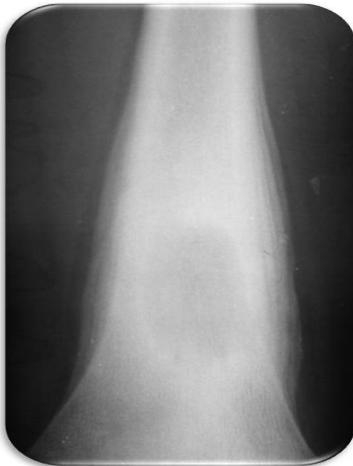

Aneurysmal Bone Cyst

site: Distal tibial

size: Involving most of distal part

matrix: Cortical expansion, radiolucent matrix, well defined, narrow zone of transition

soft tissue involvement: no peristeal reaction